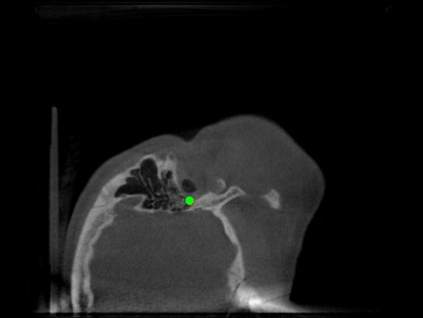

Detecting 3D landmarks on cone-beam computed tomography (CBCT) is crucial to assessing and quantifying the anatomical abnormalities in 3D cephalometric analysis. However, the current methods are time-consuming and suffer from large biases in landmark localization, leading to unreliable diagnosis results. In this work, we propose a novel Structure-Aware Long Short-Term Memory framework (SA-LSTM) for efficient and accurate 3D landmark detection. To reduce the computational burden, SA-LSTM is designed in two stages. It first locates the coarse landmarks via heatmap regression on a down-sampled CBCT volume and then progressively refines landmarks by attentive offset regression using multi-resolution cropped patches. To boost accuracy, SA-LSTM captures global-local dependence among the cropping patches via self-attention. Specifically, a novel graph attention module implicitly encodes the landmark's global structure to rationalize the predicted position. Moreover, a novel attention-gated module recursively filters irrelevant local features and maintains high-confident local predictions for aggregating the final result. Experiments conducted on an in-house dataset and a public dataset show that our method outperforms state-of-the-art methods, achieving 1.64 mm and 2.37 mm average errors, respectively. Furthermore, our method is very efficient, taking only 0.5 seconds for inferring the whole CBCT volume of resolution 768$\times$768$\times$576.